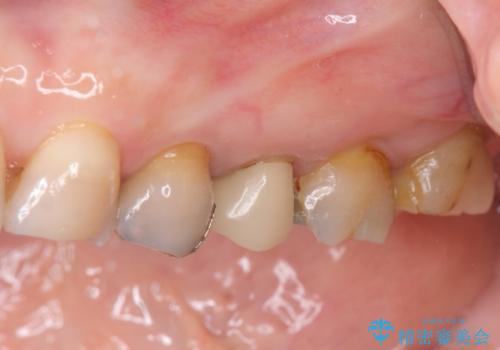

放置した虫歯 根管治療 フルジルコニアクラウン

樹脂やクラウン・銀歯の老朽化がみられるため、丁寧に除去を行い根管治療を行ったのち、歯軋り・厚みの少なさを鑑みフルジルコニアクラウンによる補綴を計画します。

- 38万円(仮歯・ファイバーコア・フルジルコニアクラウン×4)費用は治療当時の料金となります